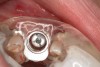

Figure 8  Primary stability of the implant achieved, facilitating a transmucosal healing approach.

Figure 8

Figure 9  Primary stability of the implant achieved, facilitating a transmucosal healing approach.

Figure 9